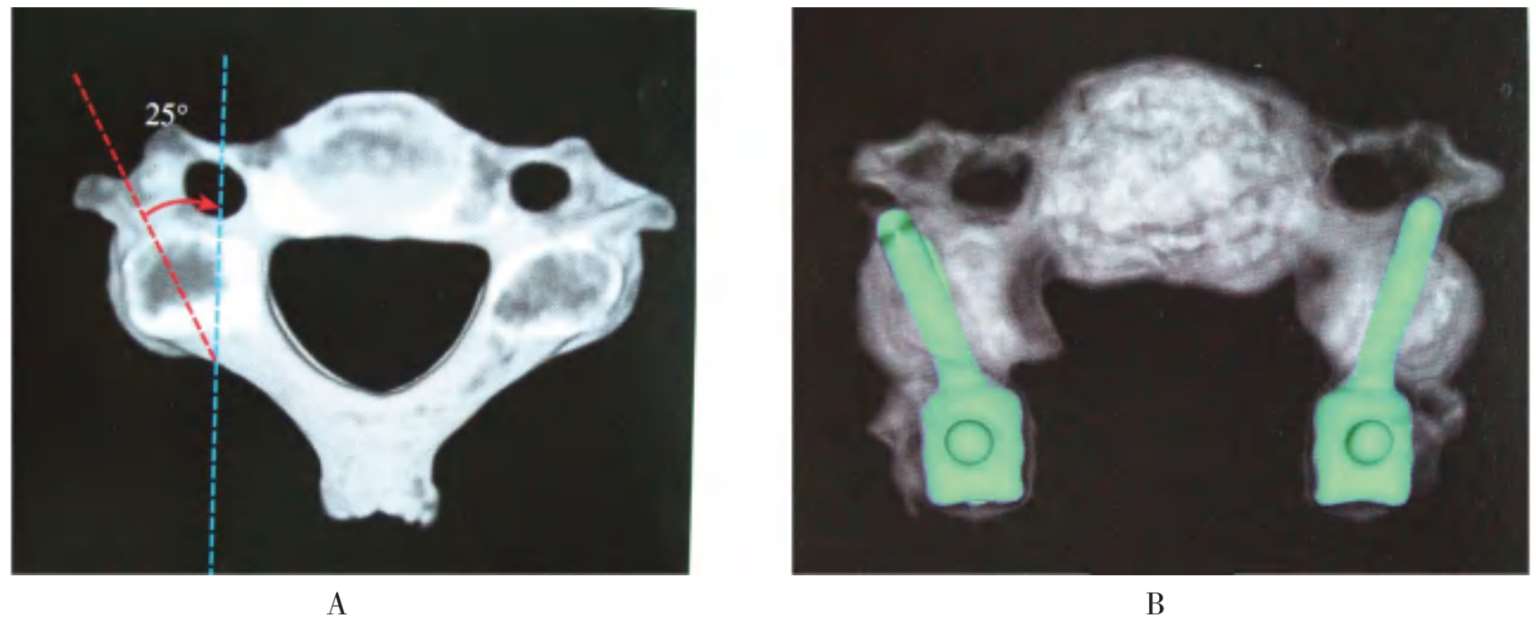

(2)侧块螺钉和椎弓根螺钉的进钉方向,如图2-69、图2-70所示。

A.在轴像上向外侧倾斜25°;B.侧块螺钉置入后的位置

图2-69 侧块螺钉的进钉方向